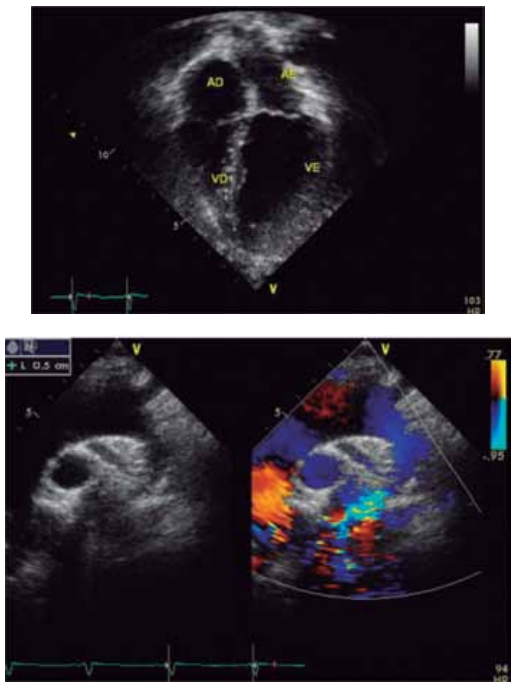

Considere as imagens a seguir.

(Arquivo pessoal; imagens usadas com autorização)

Qual é o diagnóstico provável da cardiopatia congênita ilustrada pela radiografia de tórax e a figura de ecocardiograma apresentadas desse recém-nascido?